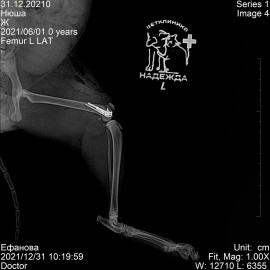

После полученной травмы от удара, кошка перестала вставать на заднюю левую лапу. После осмотра и рентгенологического исследования был поставлен диагноз: перелом левого бедра. 31.12.2021 была проведена операция: остеосинтез левого бедра.

Снимок 1 до операции.